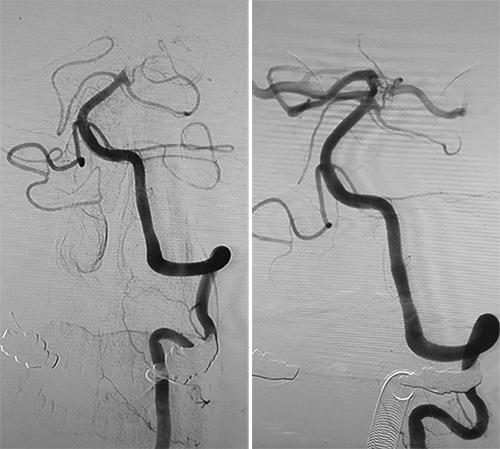

卒中小组救治成员迅速协调导管室、麻醉科、监护室,仅仅15分钟患者已送达导管室,9点30分上台并完成穿刺,9点45分造影显示基底动脉尖闭塞,10:00完成气管插管全麻,孙钦建主任医师、闫鹏主治医师立即给予基底动脉血管再通术,10点30分再通成功,造影提示基底动脉、双侧大脑后动脉显影良好,再通成功。再通后第2天患者神志转为清晰,自主呼吸,四肢活动良好,术后第4天,患者已经能与家人简单交流,肢体活动正常。

血管再通术前 血管再通术后

急性基底动脉尖闭塞是所有脑梗死中最重的一种类型,死亡率极高,即使幸运存活也可能重度残疾。该患者的抢救仅仅用了两个小时的时间,可以称得上急性卒中救治的典范。该急性重症脑梗死患者从发病到再通成功仅耗时两个多小时,得益于我院卒中中心绿色通道的实施,得益于内科ICU、麻醉科、急诊科、影像科、检验科等多科室的良好协作,也体现了我院神经介入技术已处于国内先进水平。